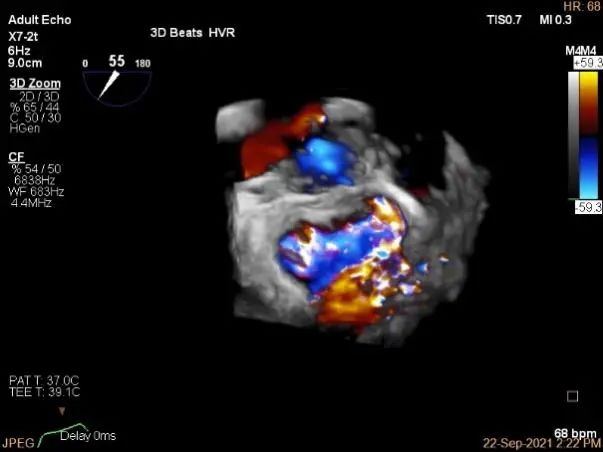

3D-color:重度MR,4级

3d-color确认残余分流情况

评估二尖瓣瓣口平均跨瓣压差:1mmHg

肺静脉血流频谱恢复正常